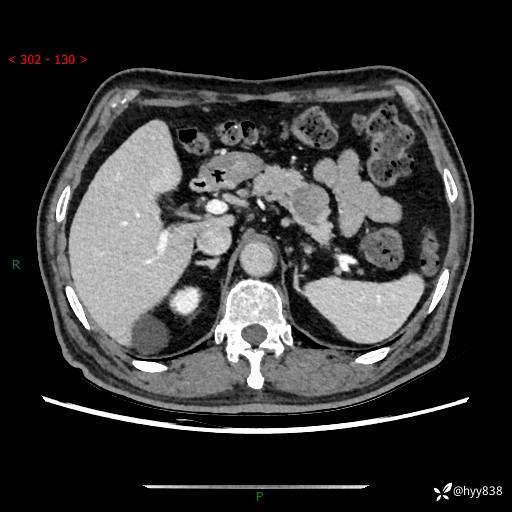

69岁/男,四肢无力3月余。胰腺囊实性占位,渐进性强化---结果公布~

【患者信息】:69岁/男

【主诉】:四肢无力3月余。

【现病史及既往史】:患者3月前无明显诱因出现四肢乏力,伴有口干、多饮、多尿等症状,无畏寒、发热、恶心、腹痛、腹泻等其他症状,于2024-06-13来我院住院治疗,完善相关辅助检查后,考虑“2型糖尿病”,予以降糖(阿卡波糖片 50mg po tid、德谷门冬双胰岛素注射液 8iu 早餐前 皮下注射)等治疗,口干、多饮、多尿较前缓解,血糖控制可;现仍存在四肢乏力,于2024-08-28来我院门诊就诊,查血钾2.88 mmol/L ,现以“低钾血症”收入我科。 本次起病以来,患者精神、饮食、睡眠良好,二便正常,近3月余体重下降约5kg。

【检查】:胰腺CT平扫+增强